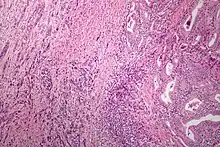

| Microscopic image of anaplastic thyroid carcinoma. H&E stain. | |

Anaplastic tumors have a high mitotic rate and frequently invades the local blood and lymphatic vessels.[5] Cellular death is frequently visualized on microscopic images.[2] The presence of regionally swollen lymph nodes in older patients in whom needle aspiration biopsy reveals characteristic vesicular appearance of the nuclei supports a diagnosis of anaplastic carcinoma. Microscopic images of ATC usually show inflammatory cells from the immune system such as T cells and macrophages.[2]

ATC is divided into several different subclasses based on its microscopic characteristics. These include sarcomatoid, squamoid, osteoclastic, paucicellular, rhabdoid, and carcinomasarcoid variants.[2] As of 2019, despite the fact that these ATC subtypes are recognized, this classification has not led to differences in management.[2] ATC is always considered to be stage IV when it is diagnosed.[6]